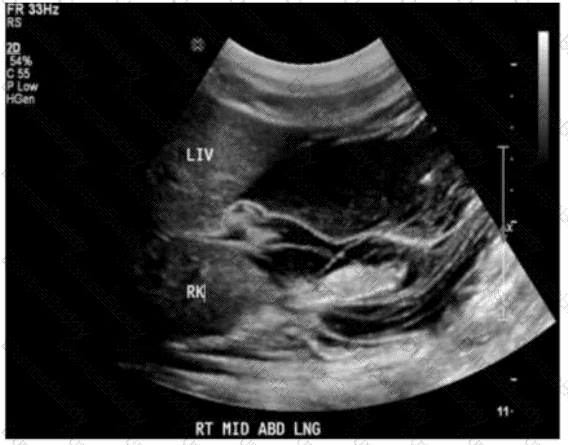

Which abnormality is depicted in this image of a patient who presents with a fever following a liver biopsy?